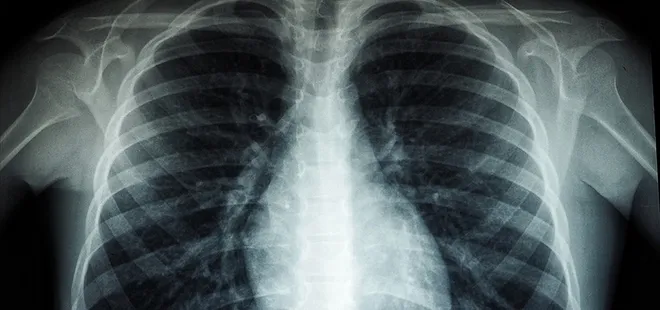

Akciğer kanseri ise akciğer dokusundaki hücrelerin kontrolsüz çoğalmasıyla oluşan ve diğer organlara yayılabilen ciddi bir hastalık olarak biliniyor. Genellikle erken evrelerde belirti vermediği için geç fark ediliyor ve bu durumda tedavi şansını azaltıyor. En önemli risk faktörü sigara kullanımı olsa da, sigara içmeyen kişilerde de bu hastalık görülebiliyor. Pasif içicilik, hava kirliliği, genetik yatkınlık ve bazı kimyasal maddelere uzun süreli temas ileri yaşta akciğer kanseri riskini artıran diğer etkenler arasında bulunuyor. Konuya ilişkin açıklamalarda bulunan Medicana Sivas Hastanesi Göğüs Hastalıkları Uzmanı Dr. Büşra Yayla Yerlikaya, öksürük ve balgam çıkarma gibi basit görünen semptomların kanserin belirtisi olabileceğini söyleyerek, "Bu hastalık, hem dünyada hem de ülkemizde kansere bağlı ölümlerin en sık nedenidir. Ne yazık ki genellikle erken evrede belirti vermediği için geç tanı alabilmekte ve bu da tedavi şansının azalmasına sebep olabilmektedir" dedi.

Akciğer kanserinin büyük bir kısmını sigara ile ilişkili olduğunu söyleyen Büşra Yayla Yerlikaya, "Bu hastalık, hem dünyada hem de ülkemizde kansere bağlı ölümlerin en sık nedenidir. Ne yazık ki genellikle erken evrede belirti vermediği için geç tanı alabilmekte ve bu da tedavi şansının azalmasına sebep olabilmektedir. Akciğer kanserlerinin büyük kısmı, neredeyse yüzde 85-90 kadarı bilindiği üzere sigarayla ilişkilidir. Günde içilen sigara sayısı ve kullanım süresi arttıkça risk de katlanarak artar. Ancak hiç sigara içmeyenlerde de pasif içicilik de en az aktif içicilik kadar önemli bir faktördür. Elektronik sigaralar ya da ısıtılmış tütün ürünleri de sanıldığı gibi güvenli değildir. Nikotin içerdikleri için bağımlılığı sürdürürler ve ekstra pek çok kimyasal daha içerirler. Uzun vadeli zararları henüz tam olarak bilinmemektedir" dedi.

Özellikle sigara içen bireyde öksürük gibi belirtiler varsa bir uzman tarafından değerlendirilmesi gerektiğini belirten, "Akciğer kanserinin en sık belirtileri ise uzun süren öksürük, balgamda kan, nefes darlığı, kilo kaybı ve göğüs ağrısıdır. Özellikle sigara içen birinde yeni başlayan ya da karakteri değişen öksürük varsa mutlaka bir göğüs hastalıkları uzmanı tarafından değerlendirilmelidir. Erken tanı her kanser türünde olduğu gibi akciğer kanserinde de hayat kurtarır. 50 yaş üzeri ve uzun süre özellikle 20 paket yıl ve daha fazla sigara içmiş kişilerde düşük doz tomografi ile tarama yapılması, hastalığın erken evrede erken tanı sağlar ve tedavi şansını ciddi şekilde artırır. Sigarayı bırakmak her yaşta faydalıdır. Bıraktıktan sonraki on yıl içinde akciğer kanseri riski büyük oranda azalır. Çalışmalar 10 yıl sonra yüzde 50, 15 yıl sonra ise yüzde 90'a kadar akciğer kanseri riskinin azaldığını göstermiştir. Sigara içen bireylerde sabahları balgam ve öksürükler mevcut oluyor. Bu durumlarda balgamın karakter değiştirmesi ve artması önemli bir belirti olabiliyor" diye konuştu.